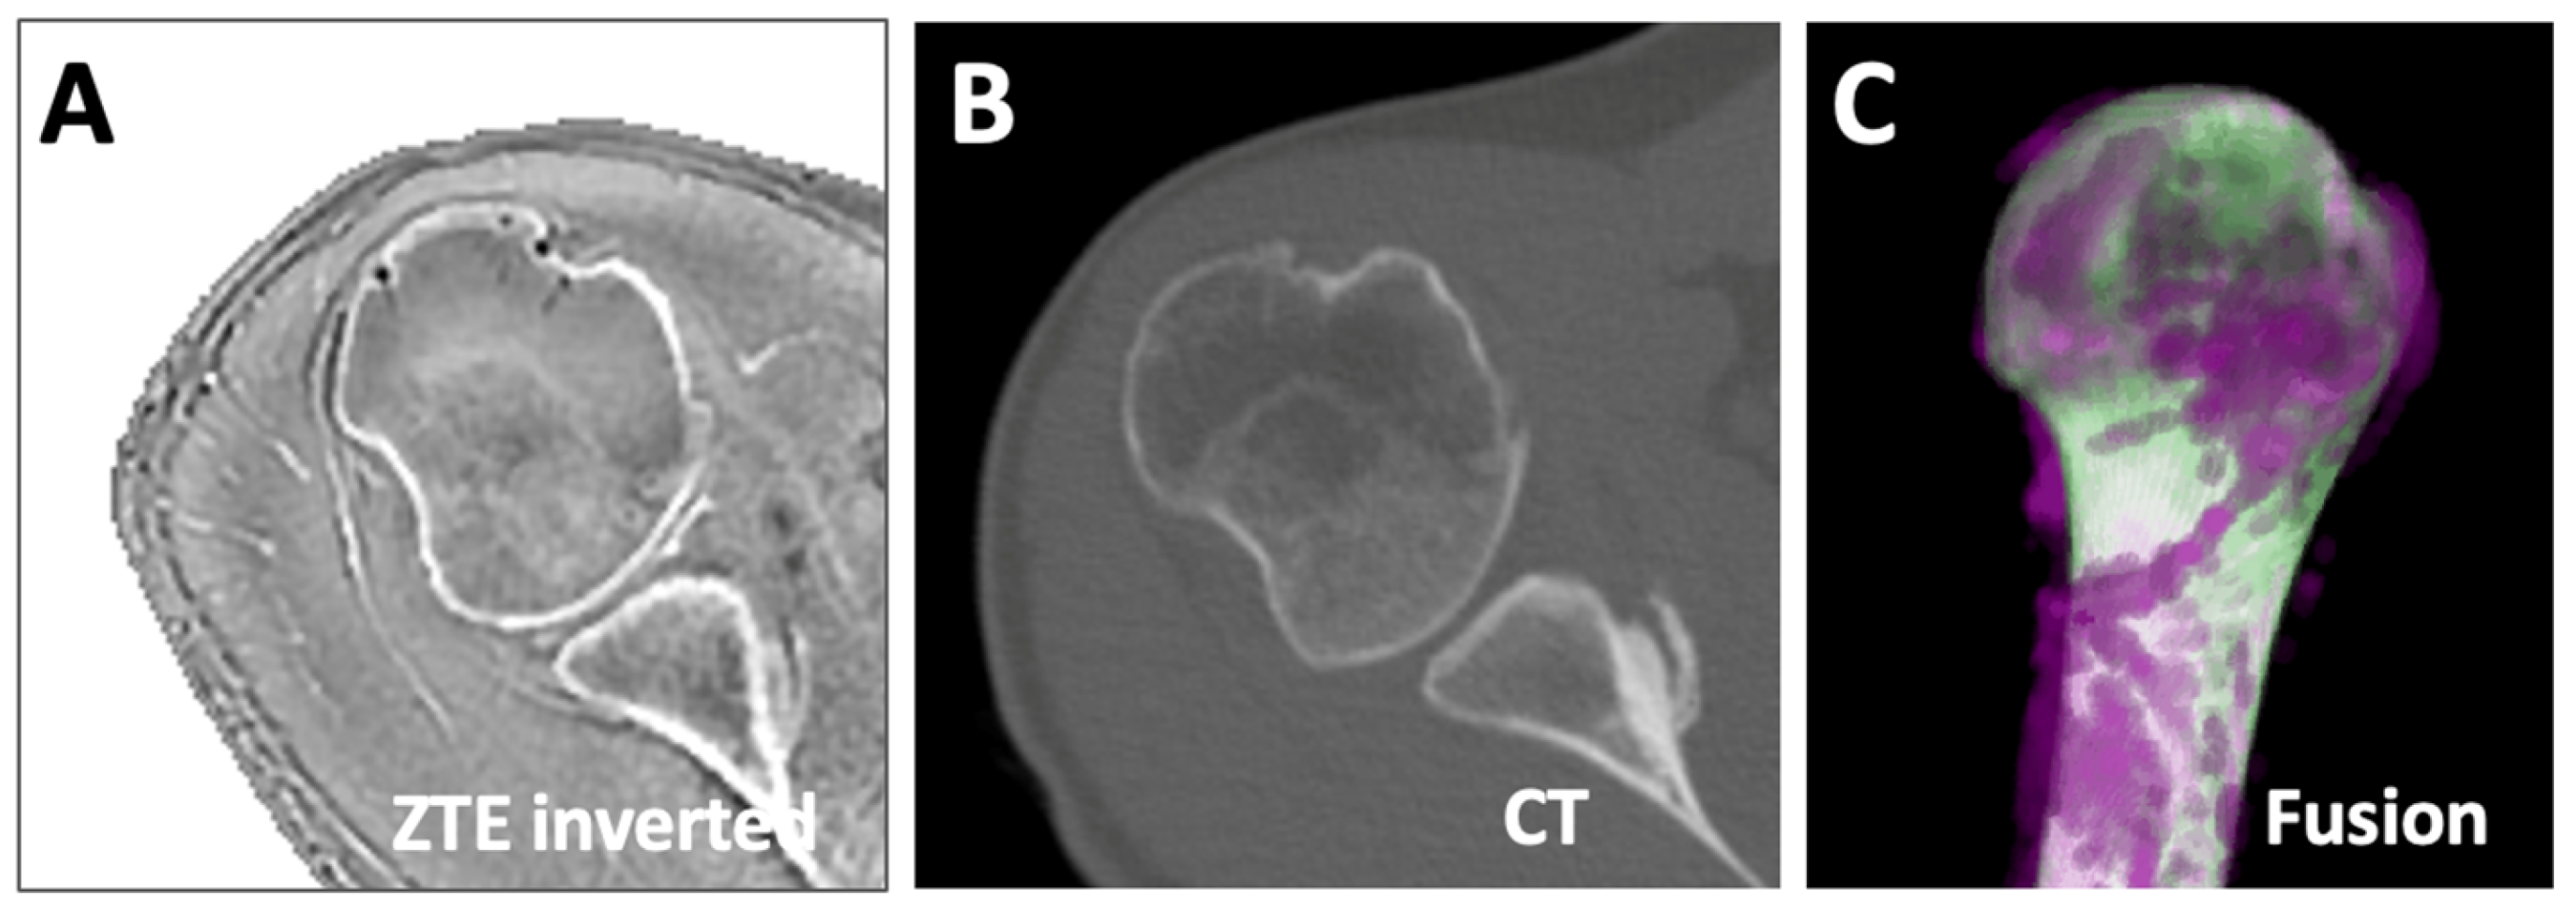

In the opportunistic data where both ZTE MRI (Figure 8A) and CT (Figure 8B) data were available from the same subject, the Dice score of the humerus segmentation using DL was 97%. We created a fused 3D rendering (Figure 8C), which shows an excellent overlap (white) between ZTE (purple) and CT (green), and is likely to yield similar values when measured for length, etc. However, this needs to be validated in additional samples.

Figure 8.

Comparison of MRI vs. CT segmentation. ZTE MRI (A) and CT (B) data of the same subject were registered and segmented (using U-Net for MRI, manually for CT). The segmented images were fused (C), showing the overlapping regions as white, and the non-overlapping regions in magenta for MRI and green for CT.